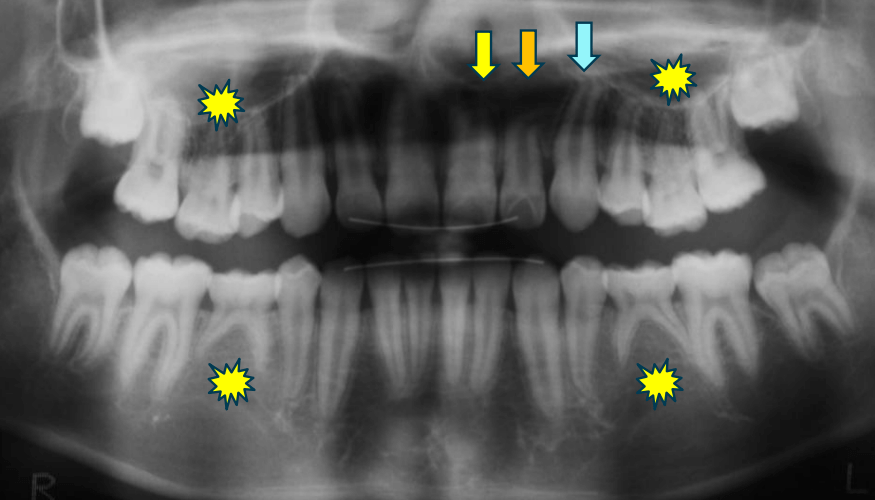

早期矯正治療 埋伏歯症例②

主訴 | 上顎前歯の位置異常に不安を抱え、歯並びと将来的な咬合状態を整える目的で来院された患者様です。 特に左側の前歯(中切歯および側切歯)の萌出が確認できないことがきっかけとなりました。 |

---|---|

診断結果 | 8歳3か月の男児。 左上1番(中切歯)と左上2番(側切歯)が埋伏し、発育方向にも異常が認められました。加えて、一部先天性欠如も確認されており、歯列全体の成長に影響を及ぼす可能性があると診断されました。 |

治療内容 |

|

治療後の経過 | 動的治療後は3〜4か月ごとの定期検診を行い、上下顎の骨の成長や第二大臼歯の萌出状況を確認しながら、本格的な矯正治療を行う |

治療期間 | 動的治療期間:約5年10か月 |

治療費用 | 460,000円(税別) |